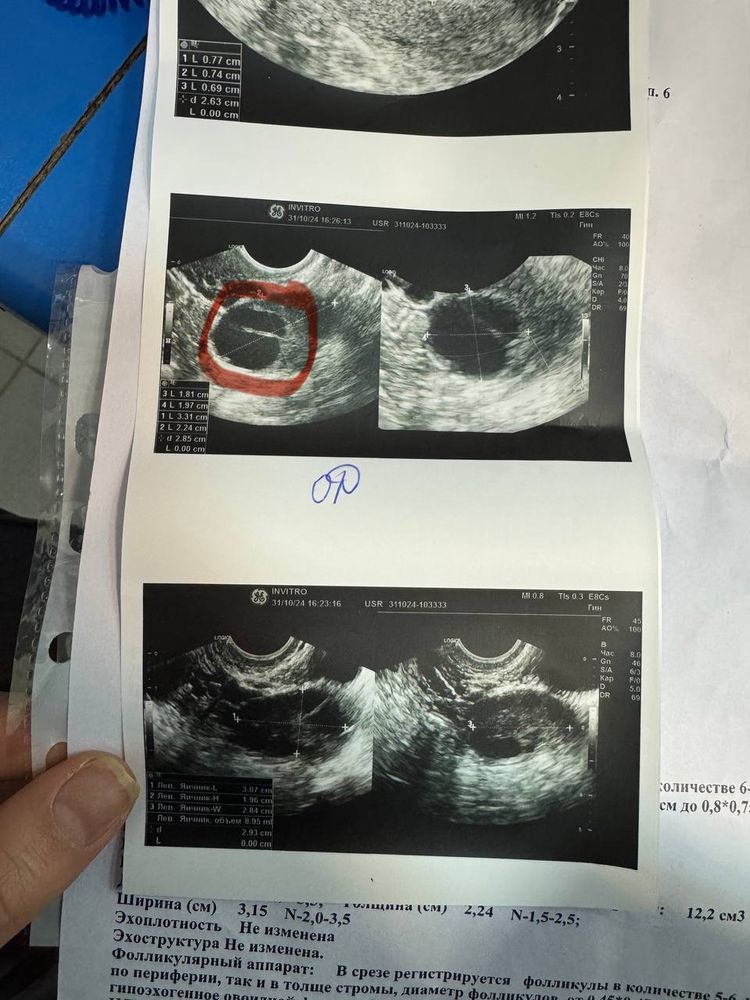

Задержка М и нет БДевочки,у меня всегда овуляция на 18ДЦ. В этот раз сходила на узи на 17ДЦ и на узи увидели ЖТ. Врач сказал, что в этот раз овуляция ранняя. Сегодня 31 ДЦ ,а месячных нет и тест делала вечером он кристально чистый(( скажите пожалуйста,что это может бы б? Было ли такое у кого нибудь ?

ALINA , еще меня смущает снимок с ЖТ по середине белая полоска какая то. Может быть такое ,что врач вообще ошибся ? И никакой овуляции не было ?

Тайный , УЗИ действительно похоже на ЖТ, а полоска,ну бывает такое, ЖТ же в принципе не может иметь ровных границ, оно как бы рваное после выхода ЯК, возможно это просто кусочек ткани болтается там..ну и ещё как вариант возможно сейчас у вас киста жёлтого тела, при таком раскладе 2 фаза может удлиниться, но это не критично..

ALINA , а как вы думаете ,вот на узи была на 17ДЦ уже вот такое ЖТ,это значит что овуляция могла быть на 15 или 16 ДЦ? Врач мне сказал что овуляция была на 14ДЦ

Тайный , ну тут уж врач слукавила, она никак не могла определить четко день овуляции..ни по размеру, ни по количеству жидкости в позадиматочном пространстве..никто же не знает лопнул у вас фолик на 10мм или на 12мм если до этого небыло фоликулометрии...у меня например тоже в один месяц фолик вырос до 13 мм и лопнул, а в другом аж до 23 мм...ещё ходит миф, что жёлтое тело после овуляции видно только через пару дней..но по факту его видно уже через сутки, проверено лично)